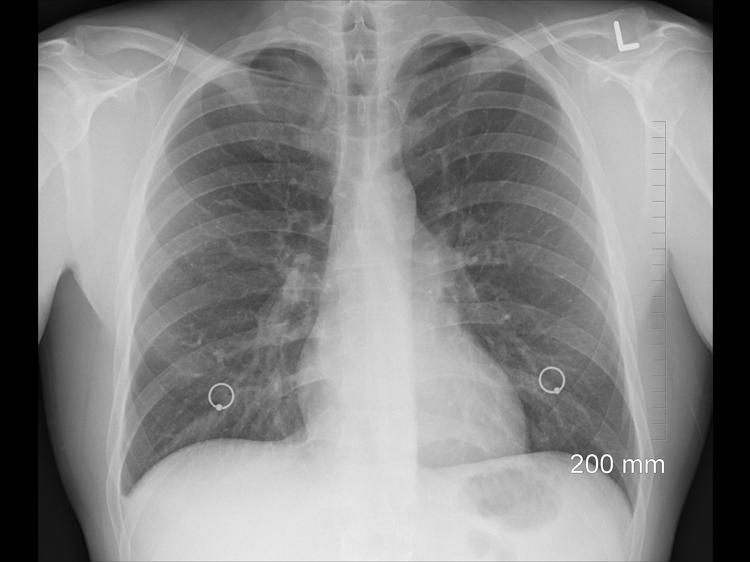

如果长期出现早起喉咙有痰的情况,不要自行判断和用药,建议按照以下3个步骤科学应对: 第一步是观察记录症状。可以准备一个小本子,记录每天早起痰的颜色、性状、量的多少,以及是否有伴随症状,比如有没有胸闷、咳嗽、发热等,这样去医院就诊时,医生能更快了解情况,做出准确诊断。 第二步是避免自行调理。很多人会自己买化痰药或者祛湿茶喝,但这样做可能不对症,比如如果是细菌感染引起的痰,喝祛湿茶是没有效果的,反而可能延误病情;如果是痰湿证,不对症的化痰药也无法解决根本问题。 第三步是及时到正规医院就诊。如果持续时间超过2周,建议到正规医院的中医内科或呼吸内科就诊,中医医生会通过看舌象、摸脉象,结合整体症状进行辨证诊断,判断是否为痰湿证;西医医生则可能会通过喉镜、胸片等检查,明确是否有呼吸道感染、支气管炎、慢性咽炎等问题,然后给出针对性的治疗建议。